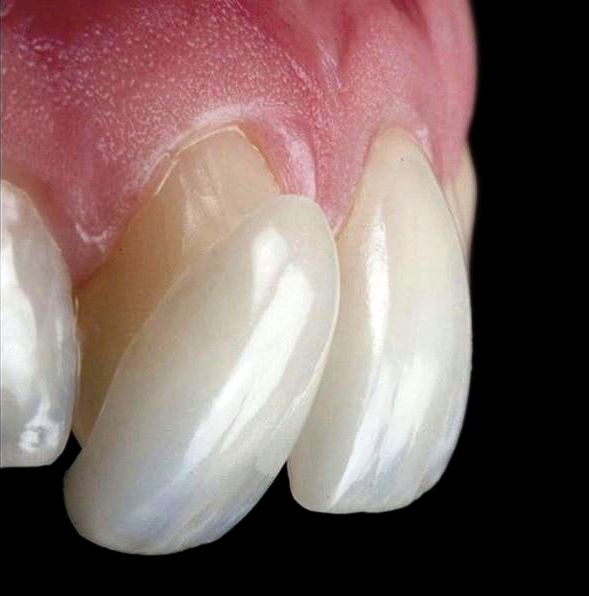

در مقابل لمینت ها روکش هایی ظریف و نازک هستند که از دوام و استحکام بالایی برخوردارند. این روکش ها روی دندان ها قرار می گیرند و ناهنجاری های خفیف دندان، مانند کج بودن و ازدحام دندان ها را پوشش می دهند. لمینت ها برای اصلاح طرح لبخند بیماران نیز مورد استفاده قرار می گیرند. شکل، رنگ و اندازه لمینت ها نیز بسته به انتخاب خود فرد می تواند تغییر کند. لمینت ها نیز مانند درمان ارتودنسی انواع مختلفی دارند و شامل لمینت های کامپوزیتی، سرامیکی و بدون تراش می شوند. جنس نمونه های سرامیکی از سرامیک و لمینت های کامپوزیتی از پلیمر است. هردو انواع لمینت ها با استفاده از تاباندن یک اشعه مخصوص به روی دندان ها چسبیده می شود. برای چسباندن برخی از انواع لمینت ها باید سطح دندان کمی تراشیده شود اما در لمینت بدون تراش جهت چسباندن لمینت ها نیازی به تراشیده شدن مینای دندان نیست.

به منظور قرار گرفتن تحت درمان لمینت نیز بیمار باید در اولین مرحله برای معاینه دهان و دندان به متخصص لمینت مراجعه کند. بعد از معاینه و مشاهده ناهنجاری های موجود در دهان و دندان بیمار متخصص تعیین می کند که چه نوع از لمینت برای درمان بیمار مناسب تر است. بسته به نوع لمینت انتخابی در صورت نیاز مقداری از سطح مینای دندان ها تراش داده خواهد شد. سپس از دندان های بیمار قالب گیری می شود و این قالب به منظور ساخت قالب نهایی به آزمایشگاه فرستاده می شود. پس از حدود دو الی چهار هفته لمینت نهایی آماده می شود. لازم به ذکر است در مدت آماده سازی لمینت نهایی بیمار از روکش های موقت روی دندان های خود استفاده خواهد کرد. زمانی که لمینت آماده می شود، متخصص لمینت دهان و دندان بیمار را به طور کامل تمیز کرده و سپس لمینت را روی دندان های بیمار قرار می دهد.

روش درمانی لمینت برای بیمارانی که دندان های کوچک و با فاصله دارند روشی مناسب است. همچنین کسانی که شکل دندان های نیش در آن ها زیبا نیست نیز می توانند از این روش درمانی برای اصلاح طرح لبخند خود استفاده کنند. لمینت در تغییر رنگ و اصلاح فرم دندان ها، اصلاح فاصله بین آن ها و پوشاندن عیوب ظاهری مانند ترک، لب پریدگی و شکستگی دندان ها بسیار مفید است، اما کسانی که مینای دندان آن ها از استحکام کافی برخوردار نیست و دندان هایشان پوسیدگی زیادی دارد، افراد زیر ۱۸ سال و یا بیمارانی که ناهنجاری های شدید در ناحیه دهان و دندان خود دارند نمی توانند از لمینت برای اصلاح طرح لبخند خود استفاده کنند.

روش درمان لمینت نیز از دندان ها در برابر ساییدگی، شکستن و ترک خوردن محافظت می کند. همچنین با استفاده از این روش می توان ظاهر نازیبای دندان ها را در صورت وجود شکستگی، لب پریدگی و تغییر رنگ بهبود داد، طول عمر دندان ها را افزایش داد و فاصله نامناسب میان دندان ها را اصلاح کرد، اما در مقابل در صورتی که متخصص لمینت در تهران و سایر شهر ها از تجربه کافی برخوردار نباشد ممکن است بیمار در معرض ابتلا به عفونت و پوسیدگی دندان قرار بگیرد و یا پس از گذشت مدت زمان کوتاهی لمینت ها دچار آسیب شده و نیاز به تعویض پیدا کنند.